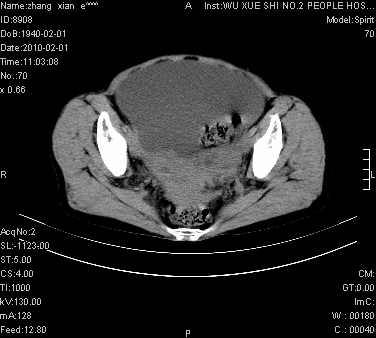

标题: CT24434:70岁 女 腹胀,腹水原因待查 [打印本页]

标题: CT24434:70岁 女 腹胀,腹水原因待查

大量腹水,脾脏囊性占位,子宫颈占位,右侧腹股沟淋巴结肿大,建议+c,先查妇科。

腹盆腔大量积液,子宫增大,子宫颈增大外形不规则,内见低密度影,膀胱后壁显示不清,右腹股沟肿大淋巴结,脾脏囊性占位,子宫颈占位,子宫颈癌?建议增强。

考虑:1、腹膜转移,大量腹水;

2、脾占位性病变;

3、左侧卵巢占位性病变,建议增强进一步检查。